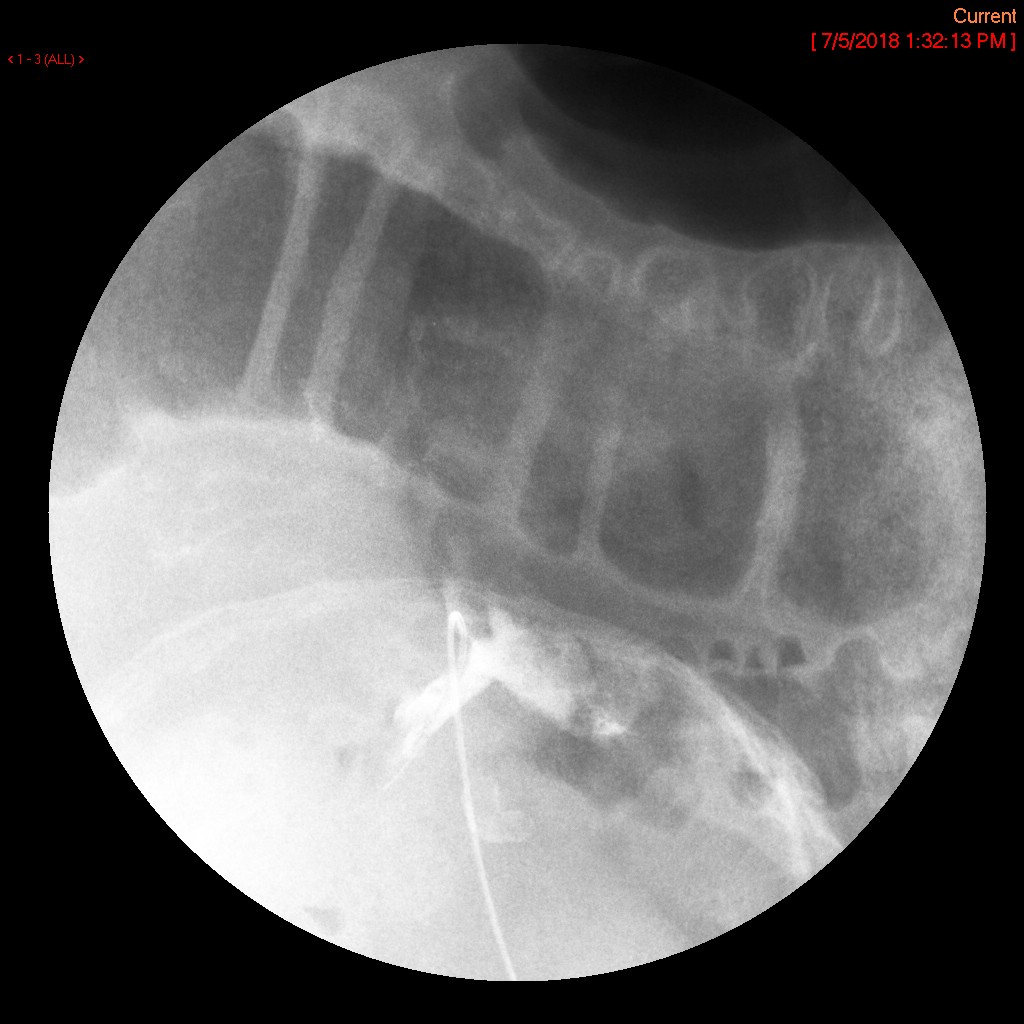

- Ensure that the most proximal side hole is inside the gastric body and obtain a spot film demonstrating the tube in the correct position

(key image 1).

- The most proximal side hole is indicated by a break in the radiopaque stripe on the tube.

- In the image above, it is indicated by the yellow arrow.